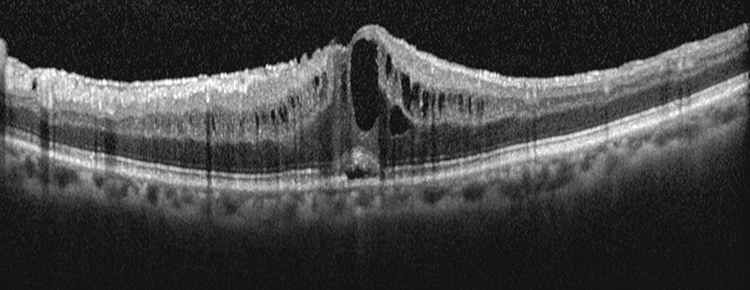

OCT will confirm the presence of CME, quantify the degree of edema and help guide the response to therapy. OCT shows central thickening with cystic spaces and loss of foveal contour. It will also help to identify any associated or contributory vitreomacular abnormalities such as ERM or VMT.